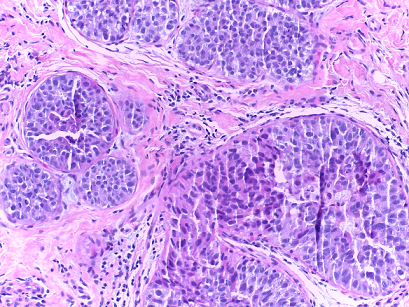

The microscopy dataset is composed of 400 training and 100 test images, with the four classes equally represented (see Fig. 2). All images were acquired in 2014, 2015 and 2017 using a Leica DM 2000 LED microscope and a Leica ICC50 HD camera and all patients are from the Porto and Castelo Branco regions (Portugal). Cases are from Ipatimup Diagnostics and come from three different hospitals (Hospital CUF Porto, Centro Hospitalar do Tâmega e Sousa and Centro Hospitalar Cova da Beira). The annotation was performed by two medical experts. Images where there was disagreement between the Normal and Benign classes were discarded. The remaining doubtful cases were confirmed via imunohistochemical analysis. The provided images are on RGB .tiff format and have a size of 2048×1536204815362048\times 1536 pixels and a pixel scale of 0.42 μ𝜇\mum ×\times 0.42 μ𝜇\mum. The labels of the images were provided in .csv format. Participants were provided with a partial patient-wise distribution of the images of the training set. The test data was collected from a completely different set of patients, ensuring a fairer evaluation of the methods. Note that the training set is an extension of the one used for developing the approach in [3].

Refer to caption

(a) Normal

(b) Benign

(c) In situ

(d) Invasive

Fig. 2: Examples of microscopy images from the BACH dataset.